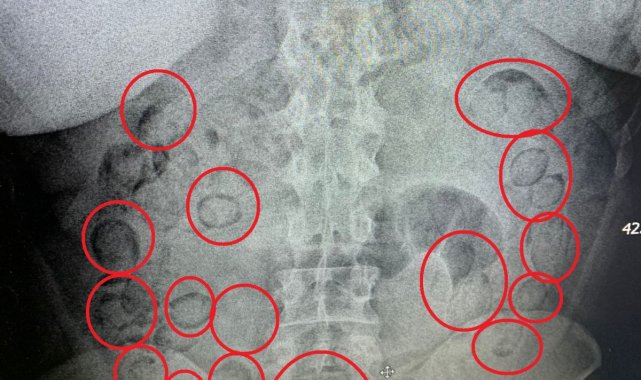

Aksaray'da narkotik ekiplerince düzenlenen operasyonda yakalanan İran uyruklu uyuşturucu tacirinin midesinde 101 parça halinde 433 gram metamfetamin maddesi ele geçirildi.Edinilen bilgiye göre, İl Emniyet Müdürlüğü Narkotik Suçlarla Mücadele Şubesi ekipleri, yaptığı analiz çalışmasında İran'ın başkenti Tahran'dan ülkeye uyuşturucu getirileceği bilgisine ulaştı. Bunun üzerine Aksaray Cumhuriyet Başsavcılığı koordinesinde harekete geçen ekipler kimliği belirlenen A.M. (20) isimli İran uyruklu şahsı teknik ve fiziki takibe aldı. Narkotik ekipleri şahsın uçakla Ankara'ya geleceği bilgisi üzerine harekete geçti. Ekipler Ankara'da uçaktan inen şahsı takibe aldı. Ankara'dan otobüse binen uyuşturucu taciri otobüsle Aksaray'a geldi. Aksaray'da E-90 karayolunda şahsın otobüsten inmesi üzerine operasyon için düğmeye basan ekipler şahsı kıskıvrak yakalayarak gözaltına aldı. Yapılan kontrollerin ardından uyuşturucuları midesine yutarak muhafaza ettiği düşünülen şahıs Aksaray Eğitim ve Araştırma Hastanesine götürülerek iç beden muayenesinden geçirildi. Tomografisi çekilen şahsın midesinde vücut dışı parçaların olduğu tespit edildi. Hastanede doktor kontrolünde ilaç içirilen İran uyruklu tacir bir süre sonra polis kontrolünde büyük tuvaletini yaparken, şahsın midesinden prezervatife sarılmış 101 küçük paket çıktı. Paketlerin içini açan polis, toplam 433 gram metamfetamin maddesi ele geçirdi. Uyuşturucu maddelere el konulurken, uyuşturucu taciri emniyetteki işlemlerinin ardından sevk edildiği adli makamlarca tutuklanarak cezaevine gönderildi.

Aksaray'da narkotik ekiplerince düzenlenen operasyonda yakalanan İran uyruklu uyuşturucu tacirinin midesinde 101 parça halinde 433 gram metamfetamin maddesi ele geçirildi.